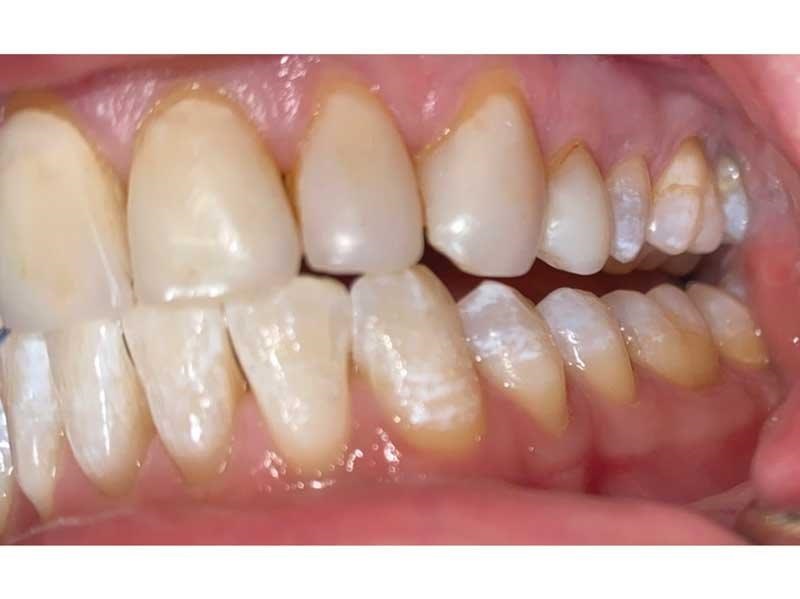

Meet Lorraine, who came into my office to “redo her bonding.” Lorraine had some upper anterior teeth done years ago with resin, which now was dull, stained and breaking down (Figs. 1–3). She had an amount of money in mind that she thought it would cost. She was very wrong.

Fig. 1

Fig. 2

Fig. 3